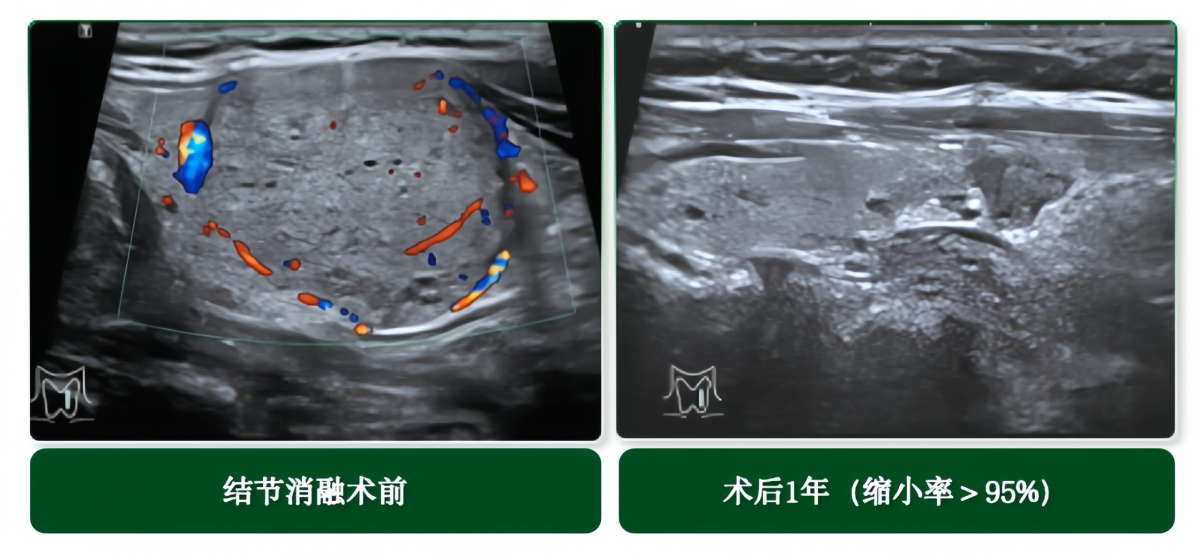

★甲状腺结节微创消融

学科与超声科紧密协作,常规开展超声引导下热消融微创治疗。该技术仅需局部麻醉,在超声实时引导下将消融针精准穿刺至结节内部,通过热能使其凝固坏死,最终结节逐渐被吸收,达到无痕、保功能、快速康复的治疗效果,学科甲状腺良性结节热消融术后1年结节体积平均约缩小90%。

适用人群:

◆产生压迫症状或影响外观的良性结节;

◆高功能腺瘤的治疗选择;

◆甲状腺癌复发或淋巴结转移病灶的备选治疗;

◆甲状腺微小癌的备选治疗。